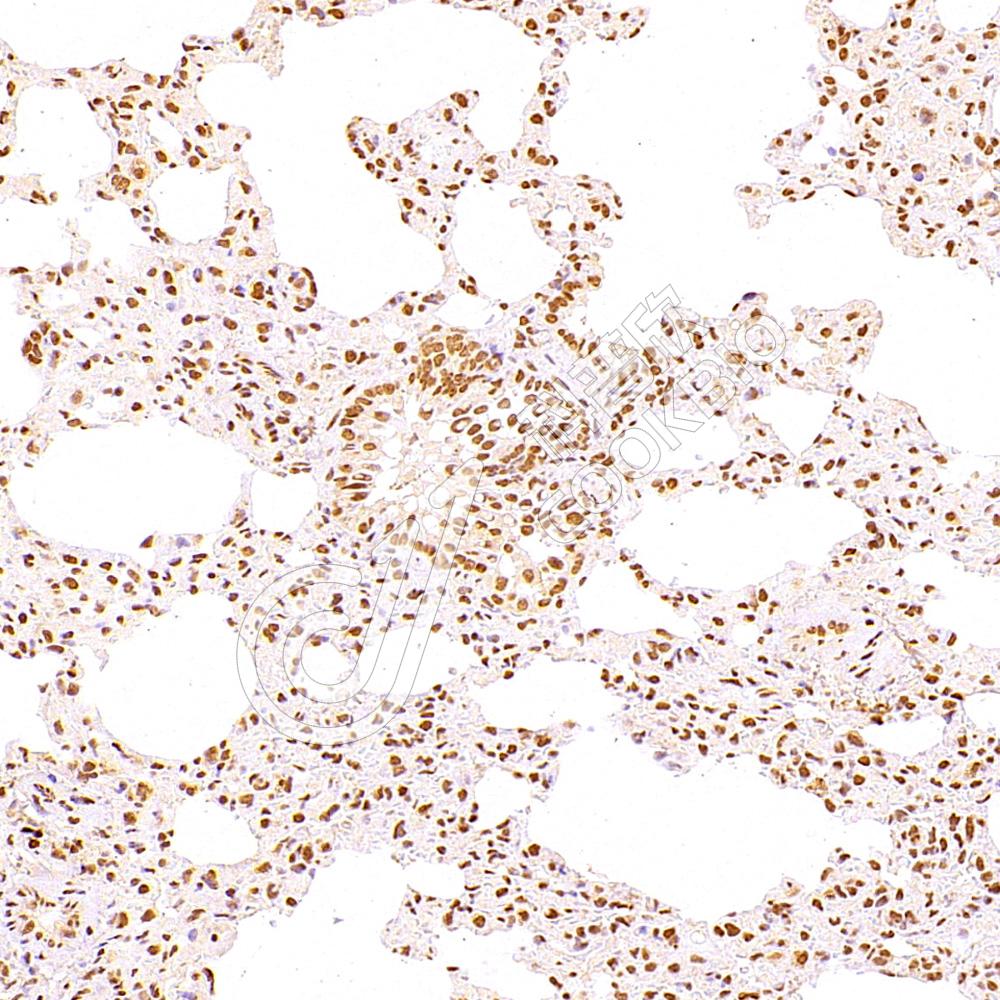

IHC检测WDR13蛋白(货号 K1337806).

样品: 小鼠肺, 4%多聚甲醛 (货号KSG1101) 固定12-24小时.

抗原修复: Tris-EDTA抗原修复液(pH 9.0) (KSG1203), 98℃, 20分钟.

—抗: 1: 5300稀释, 4℃ 孵育过夜.

二抗: S-vision免疫组化多聚二抗(山羊抗兔),即用型 (货号KB3906), 室温孵育20分钟.

样品: 大鼠肺, 4%多聚甲醛 (货号KSG1101) 固定12-24小时.